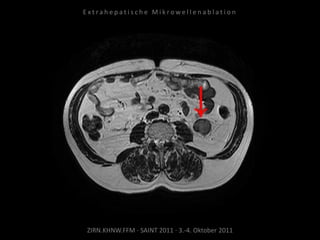

Erneute Ablation von 2 peritonealen

Metastasen am 09.09.2010.

Metastase kaudal der linken Niere:

Apikal 2 Nadelpositionen.

Kaudal 1 Nadelposition.

Metastase lateral der linken Niere:

1 Nadelposition.